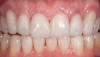

The first consideration is evaluating the substrate to which the material will be attached (Figure 1). Is it enamel? How much of the bonded surface will be enamel? How much enamel is on the tooth? Is it dentin? How much of the bonded surface will be dentin? What type of dentin will the restoration be bonded to (eg, tertiary or sclerotic dentin exhibits very poor bond strength, and bonding to this type of dentin should be avoided when possible)? Is it a restorative material (eg, composite, alloy)? These questions should be addressed for each tooth to be restored because this will be one major parameter for material selection.

Figure 1  Image of the prepared tooth. Significant dentin is exposed. The proposed length flexure and tensile stress risk is at least medium and the restoration thickness would be at least 0.9 mm. This was noted in chart.

Figure 1